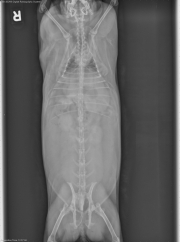

8 year old rabbit

Today’s case is in the non-domestic animal category. It’s an 8-year-old male neutered rabbit with lethargy. See what you think and post your findings in the comments section.

The colon, cecum, and small bowel are mostly empty. The margins of the liver, bladder, and cecum are well defined. There is radiodense debris within the urinary bladder. There is a fat opacity mass in the mid-abdomen, which is causing a mass effect, displacing the cecum and small bowel cranially and ventrally.

Intra-abdominal lipoma

The mass effect helps to identify a mass of lesser opacity than soft tissue. It is slightly more opaque than fat normally seen in the abdomen because of its large size. The mass may have caused ileus because of compression of the bowel.

The sediment in the urinary bladder contains calcium and is a common finding in rabbits.